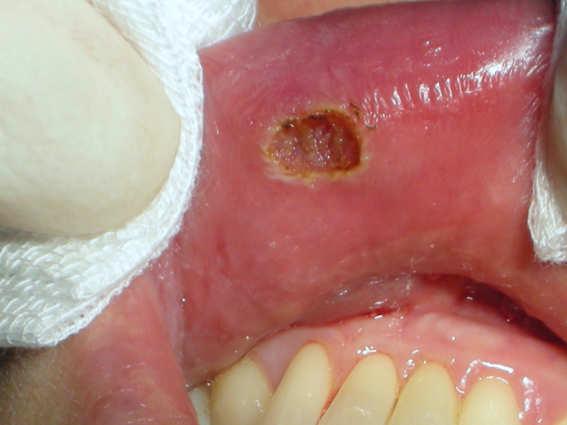

Lower lip internal

Dr. Dr. Valter Pirazzoli

Diode Laser 810nm

Power: 2,0 Watt,

CW

Fibre 400 micron